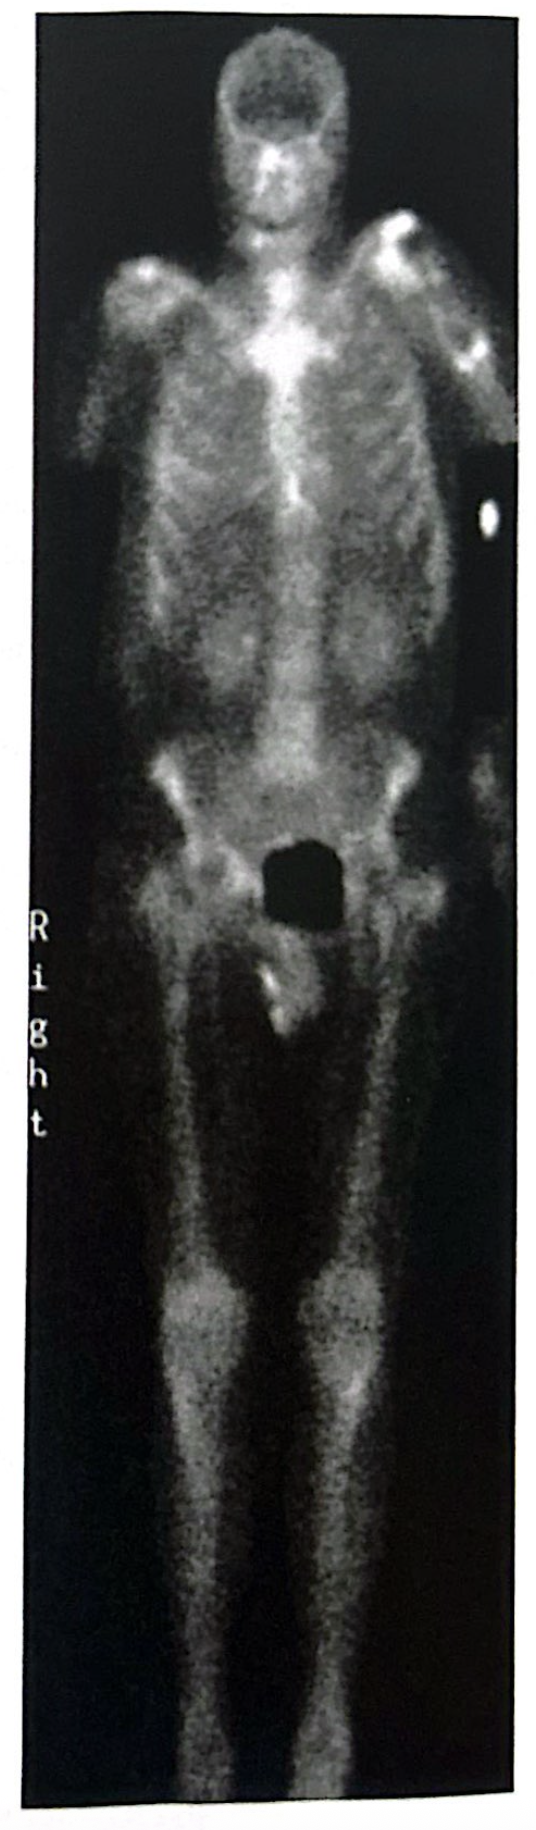

A bone scan showing relatively uniformly increased skeletal uptake of radiopharmaceutical with almost absent renal and bladder activity is usually referred to as a:

Superscan